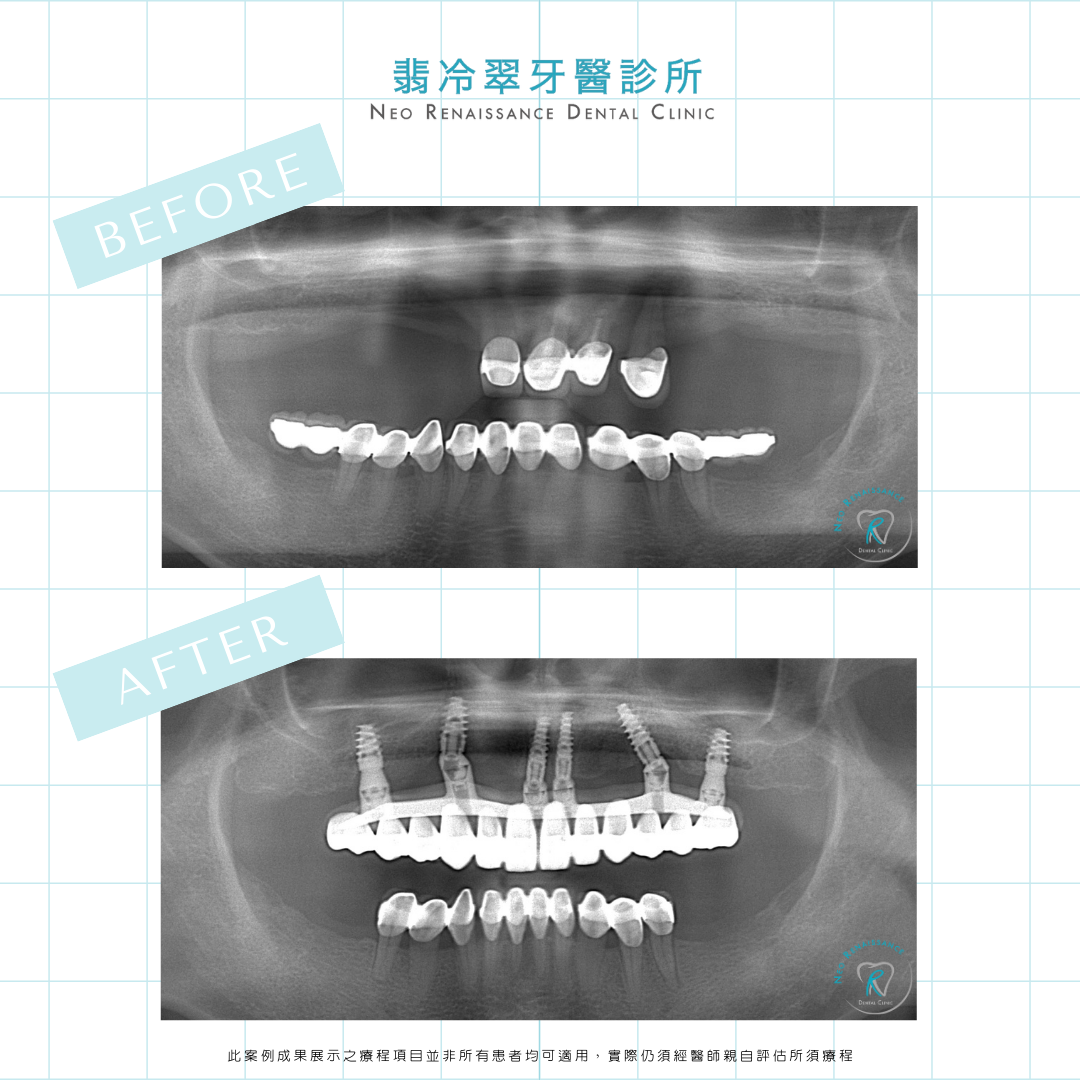

患者:賴先生

療程:ALL-ON-4®一日全口植牙重建

過去賴先生因上顎僅剩不多的四顆牙齒

已經很久無法好好進食

透過數位設備蒐集患者的全口資料

並根據患者的口腔狀況

精準模擬植牙定位及假牙的設計